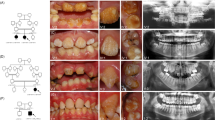

The proband of family AI-17 (arrowed in Figure 1a) presented with irregular hypoplastic AI and an autosomal dominant family history spanning four generations. Affected family members had experienced many symptomatic (eg, frequent pain) and aesthetic problems with their teeth (Figure 1b). Some individuals had received extensive restorative dental care and required multiple dental extractions. Review of the medical histories revealed no other health problems cosegregating with AI. In particular, no fragility, blistering or other skin problems were noted.

(a) Pedigree of family AI-17 illustrating segregation of the wild-type (+) and variant (−) alleles for the LAMB3 variant with the disease phenotype. The proband is marked with an arrow. Individuals who were whole-exome sequenced are marked with an asterix. (b) Clinical phenotype observed in the proband at 3 years of age. A generalised, irregular hypoplastic AI is observed with small islands of enamel evident on close inspection (arrows). These are absent from where the teeth occlude indicating that the clinical phenotype has probably been modified by post-eruptive changes. The panoramic radiograph of the proband confirms that the enamel is hypoplastic on formation. (c) Electropherogram showing the LAMB3 mutation and wild-type sequence. (d) Location of the LAMB3 change with respect to the Laminin-5 heterotrimer (based on Nakano et al).28